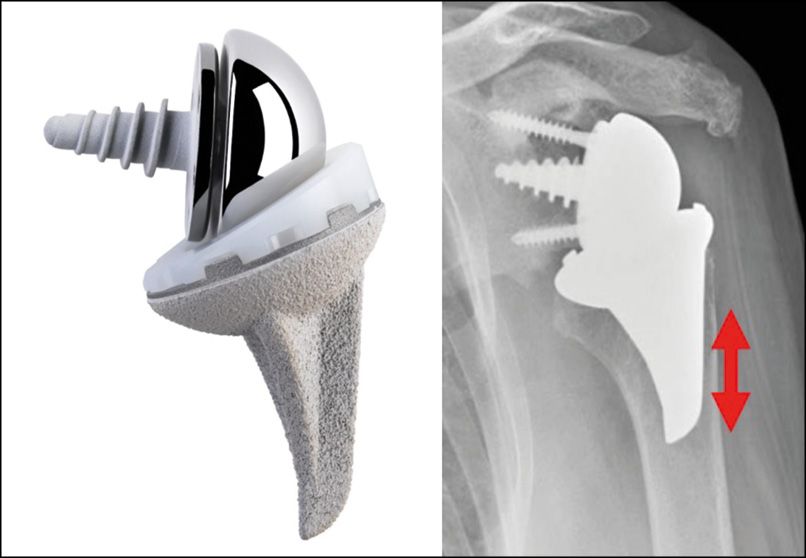

This was followed by a second wave of stemless implants that could be converted for use in both anatomical and reverse procedures: the Easytech from FX Solutions in 2012, the Nano Biomet in 2013, and the SMR S from Lima in 2014 (Fig. 5).

Inlay designs such as the TESS and Lima SMR S give satisfactory mid and long-term outcomes. [11], Adjibade D, Clark Y, Wiater J M et al. Prothèse totale d’épaule inversée sans tige : une revue systématique. JSES may 2022- 5 – 1083-1095[12] Kostretzis L, Papadopoulos P, Stemless reverse shoulder arthroplasty : a systematic review of contemporary literature, Musculoskeletal surgery 2021 apr 17 Istituto Rizzoli Onlay models give varying results: the Nano Revers from Zimmer-Biomet, introduced in 2013, was recalled in 2017 due to tilt and loosening [13] Galhoum S Mohamed et al. Anatomic and reverse stemless shoulder arthroplasty : fonctional and radiological evaluation JSEA 2022 vol 6. 1-10 The Easytech reverse onlay from FX Solutions, launched in 2012, also initially had problems with tilt and poor osseointegration, which appear to have been resolved by changing the cut from 135° to 145° and a symmetric PE (Fig. 24).